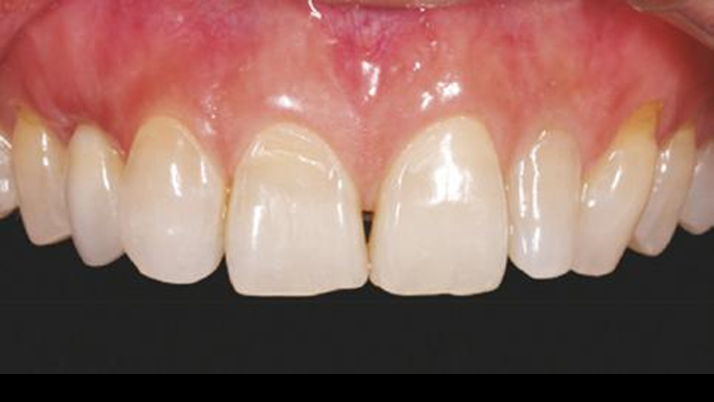

Clinical case: 3.0 mm MiNi implants placement at #12, #22

- Courtesy of Dr. Achraf Souayah, Tunise -

Keywords

Anterior esthetics, MiNi, flap elevation, minimally invasive technique, soft tissue management, esthetic zone, Dr. Achraf Souayah, anterior aesthetics, aesthetic, aesthetics, esthetic, #12, #22

Products:

MiNi implant system